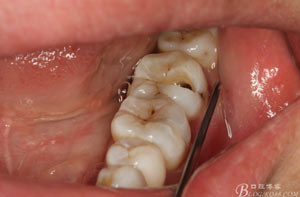

患者、申xx、女、40歲,主訴:左側(cè)下頜后牙牙齦紅腫不適數(shù)月。??茩z查:37合面有一開(kāi)髓孔。髓腔內(nèi)有一暫封小棉球,探針?biāo)枨坏撞砍鲅蔀樵谕庠褐委煂?dǎo)致底穿。x線片檢查:37頰側(cè)齦下有一枚多生牙,多生牙壓迫頰側(cè)牙根及牙體組織大量吸收。

圖2.37牙冠基本完好,松動(dòng)Ⅰ度。合面有一開(kāi)髓孔被棉球覆蓋,頰側(cè)牙齦輕度紅腫。

圖3.取出棉球口內(nèi)發(fā)現(xiàn)37合面有開(kāi)髓孔,探針出血,頰側(cè)牙齦紅腫